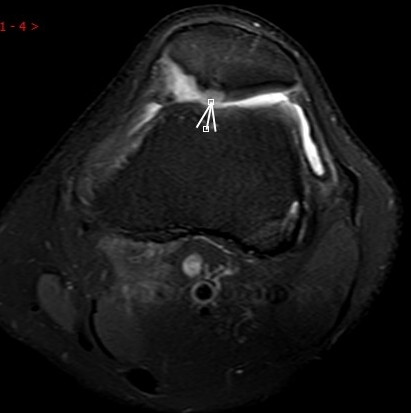

2. 運(yùn)動(dòng)后“打軟腿”——韌帶的“斷弦危機(jī)”

場景:打球急停后膝蓋不穩(wěn),走路像“踩棉花”

MRI偵查:揪出前交叉韌帶斷裂(呈“波浪狀”或連續(xù)性中斷)、內(nèi)側(cè)副韌帶損傷,防止關(guān)節(jié)“脫軌”

(內(nèi)側(cè)副韌帶損傷)